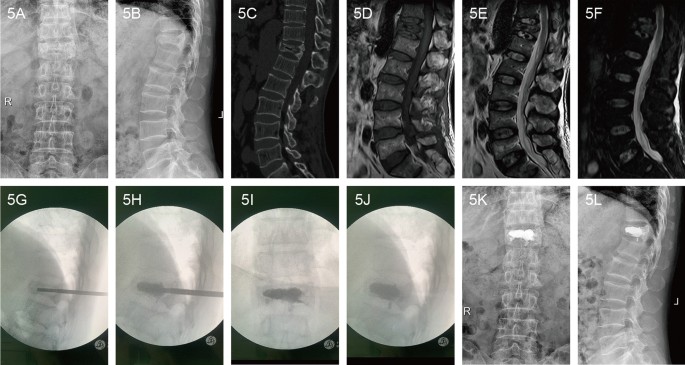

A 69-year-old male patient with Kümmell’s disease at T12 in PKP group: a Anteroposterior X-ray film before operation; b Lateral X-ray film before operation; c Intravertebral vacuum sign shown in sagittal CT image before operation; d A low signal intensity in the location of the cleft shown in sagittal T1-weighted MRI image before operation; e, f A well-defined low signal intensity in the location of the cleft shown in sagittal T2-weighted and short tau inversion recovery(STIR) MRI image before operation; g The height of the injured vertebral body was partly recovered after position reduction; h The balloons were inserted and placed inside the anterior 3/4 of the vertebral body from a lateral view, creating a cavity for the injected cement; i, j The bone cement filled the cleft without leakage in X-ray immediately after operation; k Anteroposterior X-ray film after operation; l Lateral X-ray film after operation

Compared with the pre-operation, two groups of height of the anterior edge of the injured vertebrae and Cobb’s angle at 1 day, 6 months and the final follow-up after operation were all statistically improved (P < 0.05). What’s more, the correction of injured vertebral height and kyphotic deformity in the PKP group was more obvious than that of PVP group at each time point (P < 0.05). Even though correction of injured vertebral height and Cobb’s angle in both groups gradually decreased with time after operation, there were no statistically differences between 1 day and the final follow-up after operation in each group (P > 0.05). More detailed data of patients are show in Fig. 3 and typical cases were shown in Figs. 4 and 5.